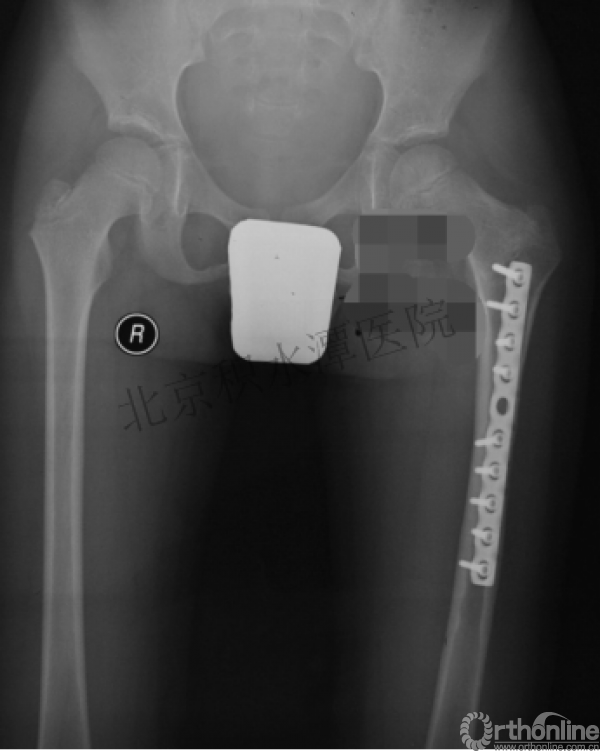

病例分享一

男孩 、5岁,初次骨折于2007年7月。

术后2年→再骨折→再次手术

钢板固定后一年

取板后再骨折→TEN

TEN取出后2个月

闭合复位再固定加尾帽

又过了4年!时间来到2015年

一年以后顺利愈合,实则危机四伏

数月后再骨折!牵引!

髋人字支具

外固定架术后一年

整整11年!是否治疗终结?

病人的付出?医生当反思!